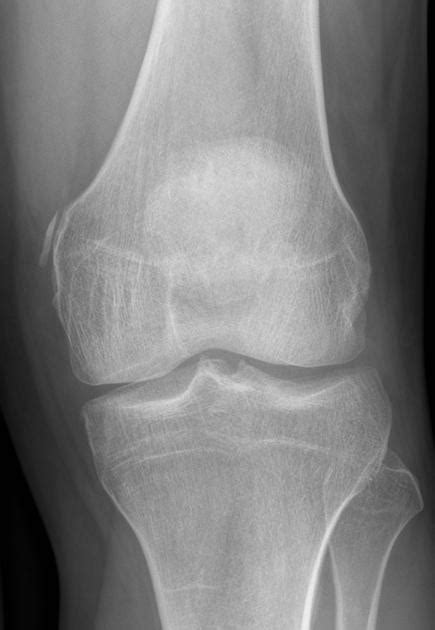

Whether it originates in the medial collateral ligament (mcl) of the knee or the medial head of the gastrocnemius muscle or. Most of the cases of pellegrini stieda lesions are not symptomatic, and pellegrini stieda syndrome is said to exist when the lesion becomes symptomatic i.e. One presumed mechanism of injury is. It is a common incidental finding on knee radiographs. Related online courses on physioplus. Lesion is named after italian and german surgeons 'augusto pellegrini' and 'alfred stieda' respectively. Ossification in or near the tibial collateral ligament (medial femoral collateral ligament) adjacent to the margin of the medial femoral condyle. #foamed #foamrad #radiology #rad #elearnrad #voxelz #varunbabu #drbabu.

Whether it originates in the medial collateral ligament (mcl) of the knee or the medial head of the gastrocnemius muscle or. Lesion is named after italian and german surgeons 'augusto pellegrini' and 'alfred stieda' respectively. The pellegrini stieda syndrome is when there is associated pain and movement restriction and is a combination of the imaging and clinical findings. Related online courses on physioplus. Learn about this soft tissue calcification around the knee joint. Lesion may mimic tendinous calcification in reactive arthritis which is associated with. It is a common incidental finding on knee radiographs. Posted on march 19, 2018 by ryj17001. Whether it originates in the medial collateral ligament (mcl) of the knee or the medial head of the gastrocnemius muscle or. Most of the cases of pellegrini stieda lesions are not symptomatic, and pellegrini stieda syndrome is said to exist when the lesion becomes symptomatic i.e. Pain and restriction of movements. Entrapment of the torn end in the medial compartment. Ossification in or near the tibial collateral ligament (medial femoral collateral ligament) adjacent to the margin of the medial femoral condyle.